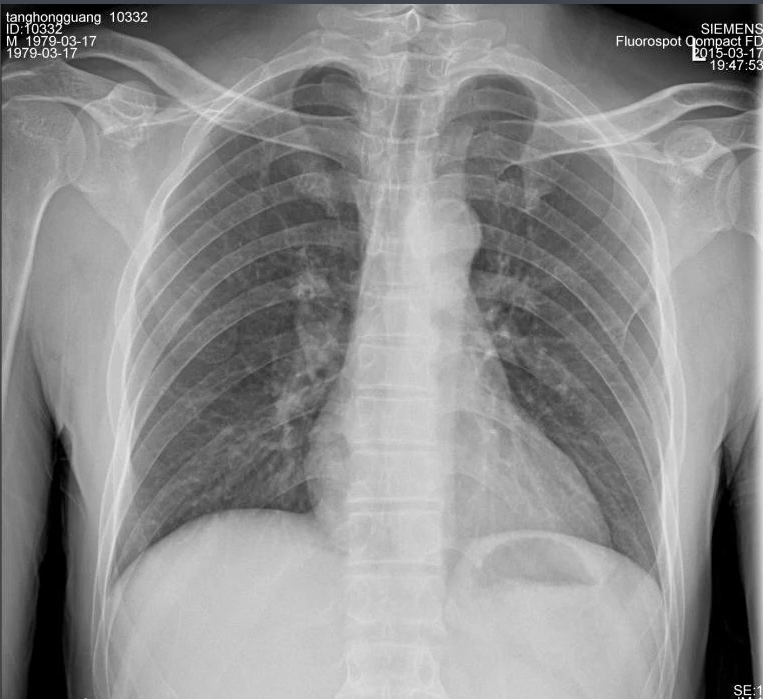

X射線,是一種頻率極高,波長極短、能量很大的電磁波。具有穿透性,但人體組織間有密度和厚度的差異,當(dāng)X射線透過人體不同組織時,被吸收的程度不同,經(jīng)過顯像處理后即可得到不同的影像。下面那我們來聊一聊關(guān)于X射線的三大特性分別是哪些。

X射線因其波長短,能量大,照在物質(zhì)上時,僅一部分被物質(zhì)所吸收,大部分經(jīng)由原子間隙而透過,表現(xiàn)出很強(qiáng)的穿透能力。X射線穿透物質(zhì)的能力與X射線光子的能量有關(guān),X射線的波長越短,光子的能量越大,穿透力越強(qiáng)。X射線的穿透力也與物質(zhì)密度有關(guān),利用差別吸收這種性質(zhì)可以把密度不同的物質(zhì)區(qū)分開來 。

X射線同可見光一樣能使膠片感光。膠片感光的強(qiáng)弱與X射線量成正比,當(dāng)X射線通過人體時,因人體各組織的密度不同,對X射線量的吸收不同,膠片上所獲得的感光度不同,從而獲得X射線的影像 。